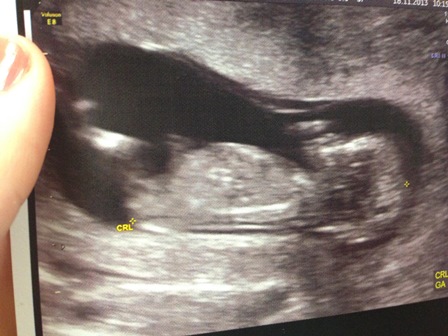

Ok so I have to apologise, this bub is a mover and groover and would barely stay still so I dont think I've got any good pictures of a nub.. was hoping a few of you might have an opinion on what you see though? Any feedback is much appreciated!! Attachment 15352Attachment 15353

I've got one side profile and one potty shot :) This was a scan at 13 weeks exactly :)